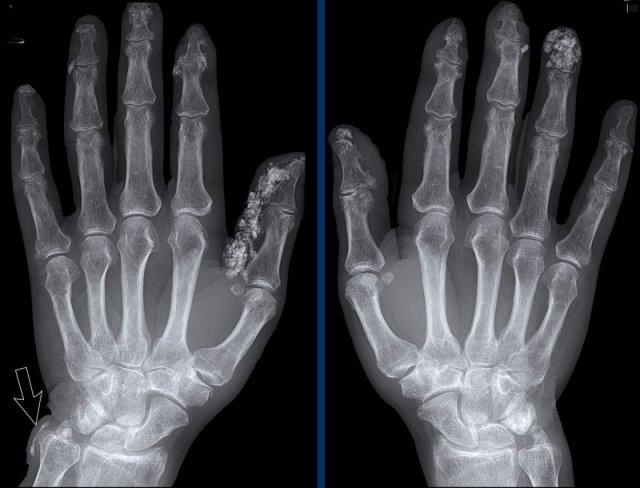

Ngón xúc xích

Hình ảnh điển hình của viêm ngón tay (dactylitis) “ngón xúc xích” với phù nề mô mềm và biến dạng bút chì trong cốc tại khớp liên đốt xa (DIP) 1-2 và 5 của bàn tay trái ở bệnh nhân viêm khớp vảy nến.

Lưu ý rằng các khớp bàn ngón tay (MCP) không bị tổn thương (khác với viêm khớp dạng thấp).

Vôi hóa mô mềm lan rộng tại các đốt ngón xa ở bệnh nhân xơ cứng bì.

Lưu ý các vôi hóa cạnh đầu xa xương trụ (mũi tên).

Không có dấu hiệu tổn thương sụn khớp.

Vôi hóa mô mềm kín đáo nhưng thô ráp tại phần xa nhất của ngón tay ở bệnh nhân xơ cứng bì.

Không ghi nhận tiêu xương đầu chi hay các dấu hiệu bất thường khác.

Tiêu xương đầu chi trong Xơ cứng bì

Tiêu xương đầu chi nặng tại đầu ngón tay của ngón 1-3 ở bệnh nhân xơ cứng bì (mũi tên). Lưu ý hiện tượng tiêu hủy mô mềm ở phần xa.

Tiêu xương đầu chi là dấu hiệu X-quang chỉ sự phá hủy xương tại các đốt ngón xa, xảy ra ở 6–65% bệnh nhân xơ cứng bì.